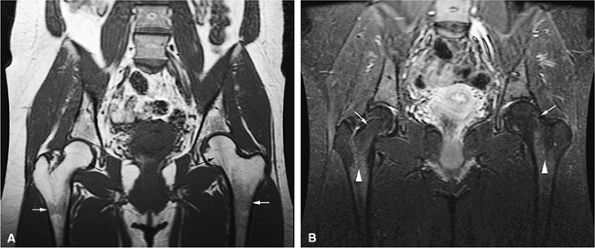

FIGURE 13.36 ● (A) An anteroposterior radiograph of the pelvis is negative for lymphomatous involvement. (B) On a T1-weighted coronal image of the pelvis, the proximal femurs and lower lumbar spine (arrows) display nonspecific low signal intensity. The fatty marrow of the epiphysis and greater trochanter is spared. (C) On a coronal STIR image, there is high-signal-intensity patchy nodularity of lymphomatous marrow involvement in the pelvis, proximal femurs, and lumbar spine (arrows). The spared yellow marrow of the greater trochanter and femoral epiphysis appears black.

|